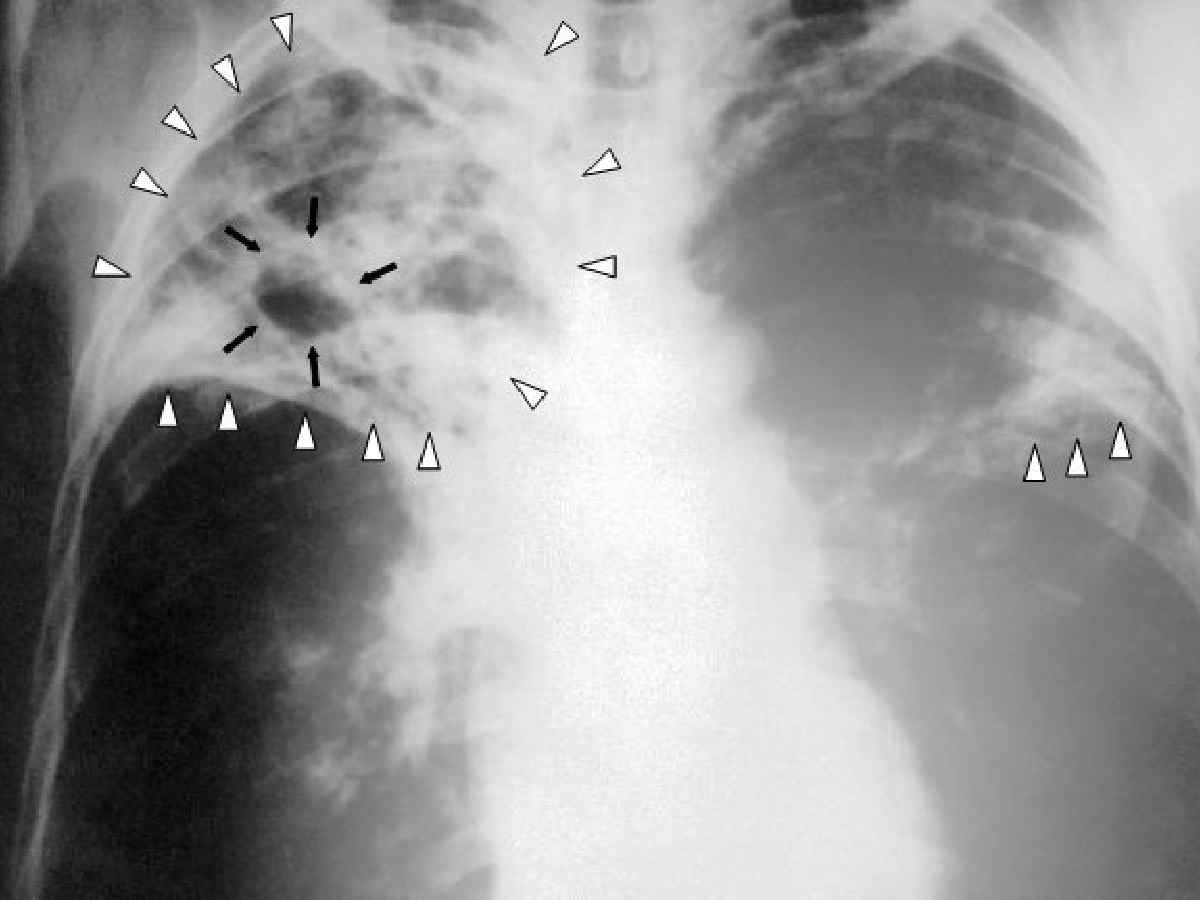

Once thought to be under control, tuberculosis (TB) has made a worrying comeback in the national capital. According to the Annual Report on Registration of Births and Deaths in Delhi 2024, 4.86% of all recorded deaths in the city last year were caused by TB — up from 3% in 2020. This sharp rise, nearly doubled in just four years, reflects a resurgence of an old epidemic driven by drug resistance, overcrowding, poor treatment adherence, and systemic gaps in healthcare and awareness.